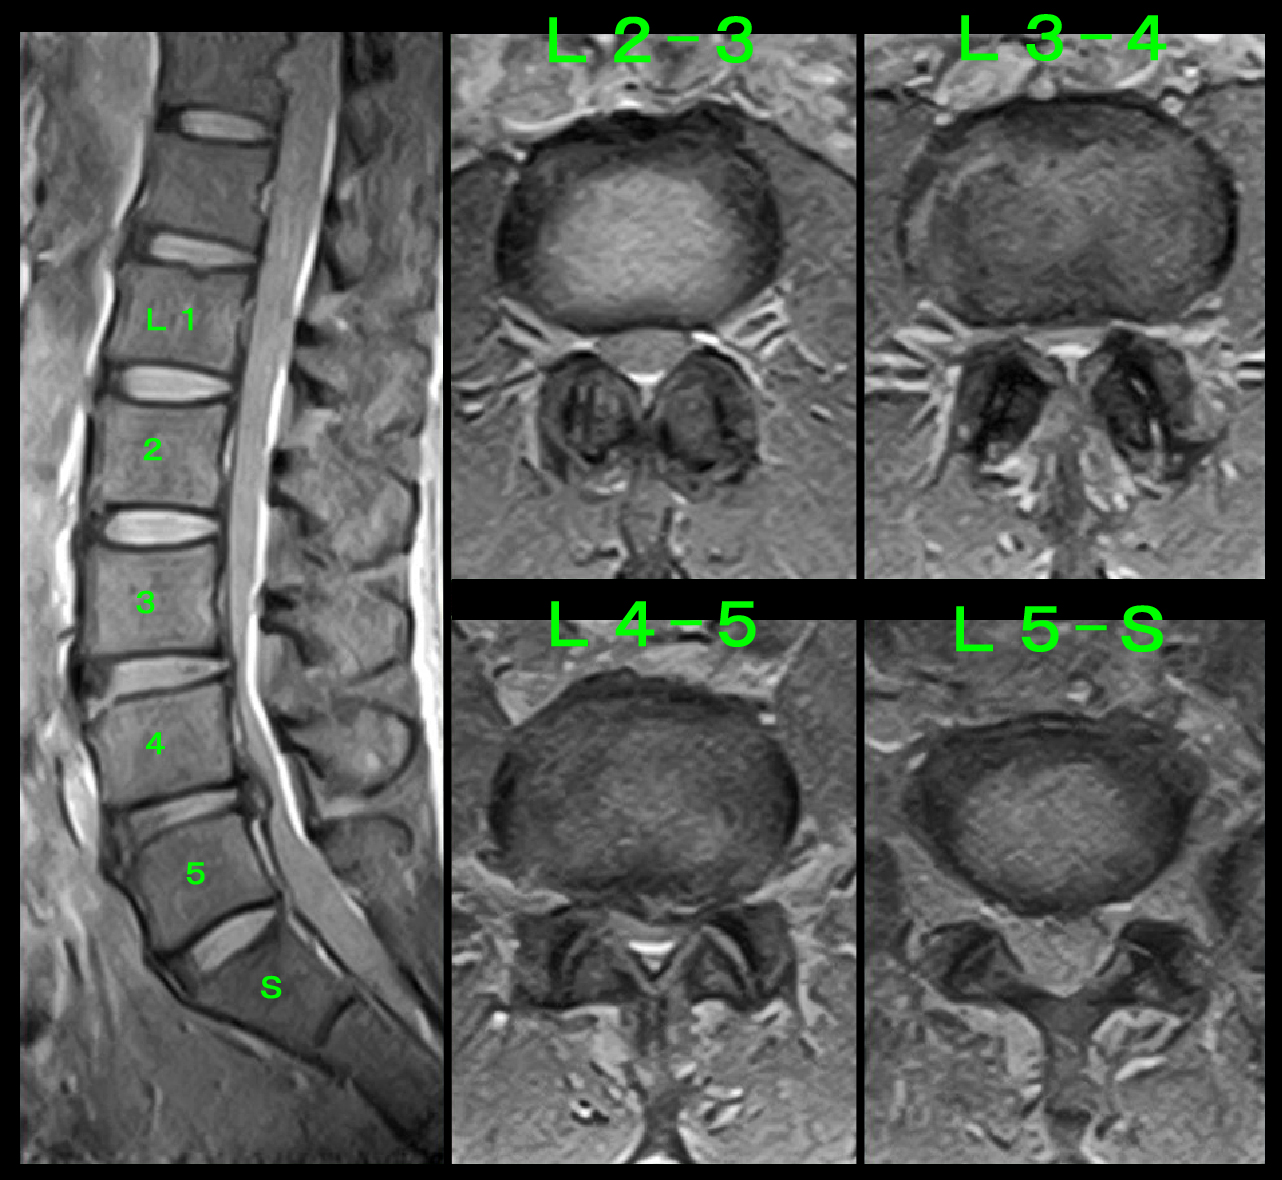

熊耳MRI検査.jpg

腰椎MRI検査ではL34とL45に軽度~中等度の脊柱管狭窄の所見が確認され(赤矢印)、通常ではこの程度の脊髄の圧迫では下垂足を呈することはまれですが、問診・診察からはそれ以外の可能性はないと判断しました。当院では下垂足の患者さんを腰椎のブロック注射により症状の改善がえられた患者さんが何名もいますが、前脛骨筋の神経はL34とL45から出てくる神経で、その2つの神経に1週ごとに3回ブロックを行うことを勧め、施行しています。